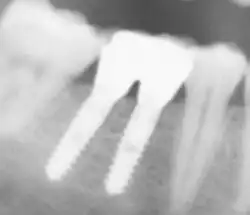

Röntgenbild eines Zahnimplantates in Regio 26 unmittelbar nach internem Sinuslift

Röntgenbild eines Zahnimplantates in Regio 26 unmittelbar nach internem Sinuslift -

Komplikationen

Im Vordergrund der Komplikationen stehen alle Faktoren, die eine Infektion im Implantationsbereich begünstigen. Zahnimplantate unterliegen der Gefahr einer Periimplantitis, einer Entzündung des Knochengewebes um das Zahnimplantat herum. Die Verbindung zwischen Implantat und Knochen ist nahezu ausschließlich durch bakterielle Einflüsse zerstörbar (Auflösung der Knochenmatrix durch Matrix-Metalloproteasen, MMPs). Die Ursache ist entweder auf Operationsfehler oder auf eine ungenügende Mundhygiene des Patienten zurückzuführen. Die Periimplantitis führt zu einem Knochenabbau, der letztendlich den Ausfall des Implantats bewirkt. Eine Zahnimplantation wird als Misserfolg gewertet, wenn das Implantat mobil ist oder einen periimplantären Gewebsschwund von mehr als 1 mm im ersten Jahr aufweist. Eine Periimplantitis kann durch prophylaktische Maßnahmen zusammen mit einer Antibiotikatherapie behandelt werden. Eine Periimplantitis ist auf einer Röntgenaufnahme zu erkennen.

Bei zusammengesetzten Implantaten befinden sich zwischen dem eigentlichen Implantat und dem Aufbau (Abutment) Spalten und Hohlräume, in die Keime aus der Mundhöhle eindringen können. Später gelangen diese Keime wieder in das angrenzende Gewebe und können so eine Periimplantitis verursachen. Als Prophylaxe sollten diese Implantatinnenräume versiegelt werden.[73]